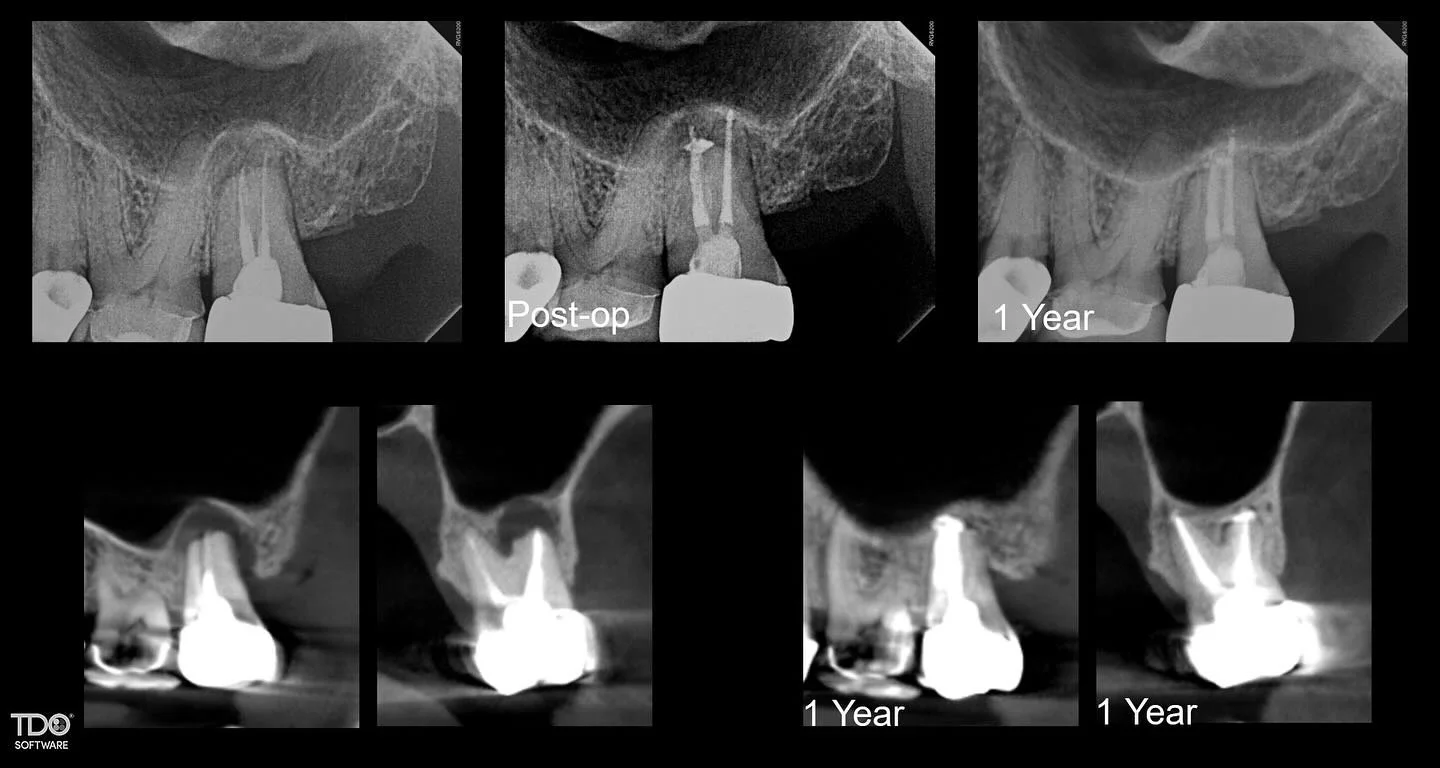

I am a board-certified endodontist with advanced specialty training and an academic interest in diagnostic reasoning, retreatment, and microsurgical endodontics. My work emphasizes CBCT-guided decision-making, interdisciplinary collaboration, and evidence-based care in complex clinical scenarios.